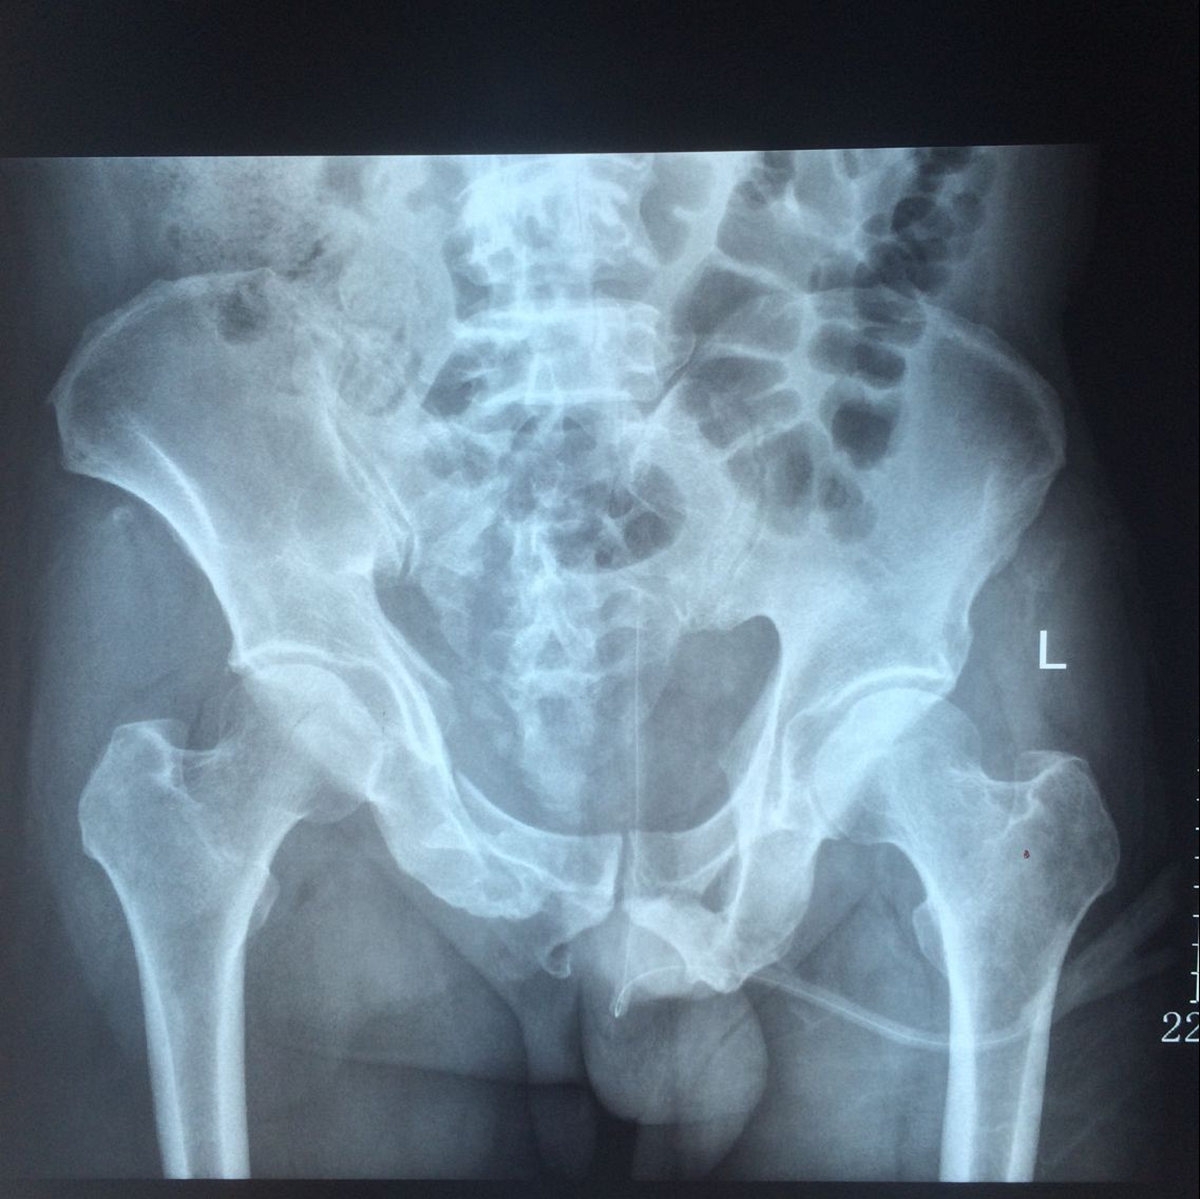

該患者為雙前臂橈尺骨遠(yuǎn)端多發(fā)粉碎骨折,骨盆多發(fā)骨折(雙側(cè)恥骨上下支骨折、右髖臼骨折、右骶骨粉碎性骨折),腰椎多發(fā)骨折。骨盆骨折的手術(shù)治療在創(chuàng)傷骨科而言,難度大、技術(shù)要求高,較容易出現(xiàn)相關(guān)并發(fā)癥。

患者骨盆骨折術(shù)前X片及CT片情況